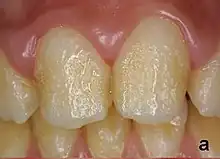

Enamel hypoplasia can take a variety of forms, but all types are associated with a reduction of enamel formation due to disruption in ameloblast production.[1] One of the most common types, Pitting Enamel Hypoplasia (PEH), ranges from small circular pinpricks to larger irregular depressions.[2] Pits also vary in how they occur on a tooth surface, some forming rows and others more randomly scattered.[3] PEH can be associated with other types of hypoplasia, but it is often the only defect observed.[4] Causes of PEH can range from genetic conditions to environmental factors, and the frequency of occurrence varies substantially between populations and species, likely due to environmental, genetic and health differences. The most striking example of this is in Paranthropus robustus, with half of all primary molars, and a quarter of permanent molars, displaying PEH defects, thought to be caused by a specific genetic condition, amelogenesis imperfecta.[1]

Each pit is linked to the ceasing of ameloblasts at a particular point in enamel formation. Sometimes, only a couple of ameloblasts stop forming enamel, leading to small PEH defects, with large pits forming when hundreds of these enamel-forming cells stop production.[6] This does not occur in other forms of enamel hypoplasia, such as linear and plane-form, in which all ameloblast activity is affected.[4] Typically with PEH described in archaeological reports, researchers can not specify a cause, with a non-specific stress often concluded. However, in modern clinical studies it is often possible to suggest a cause and these can include the following conditions:[1]